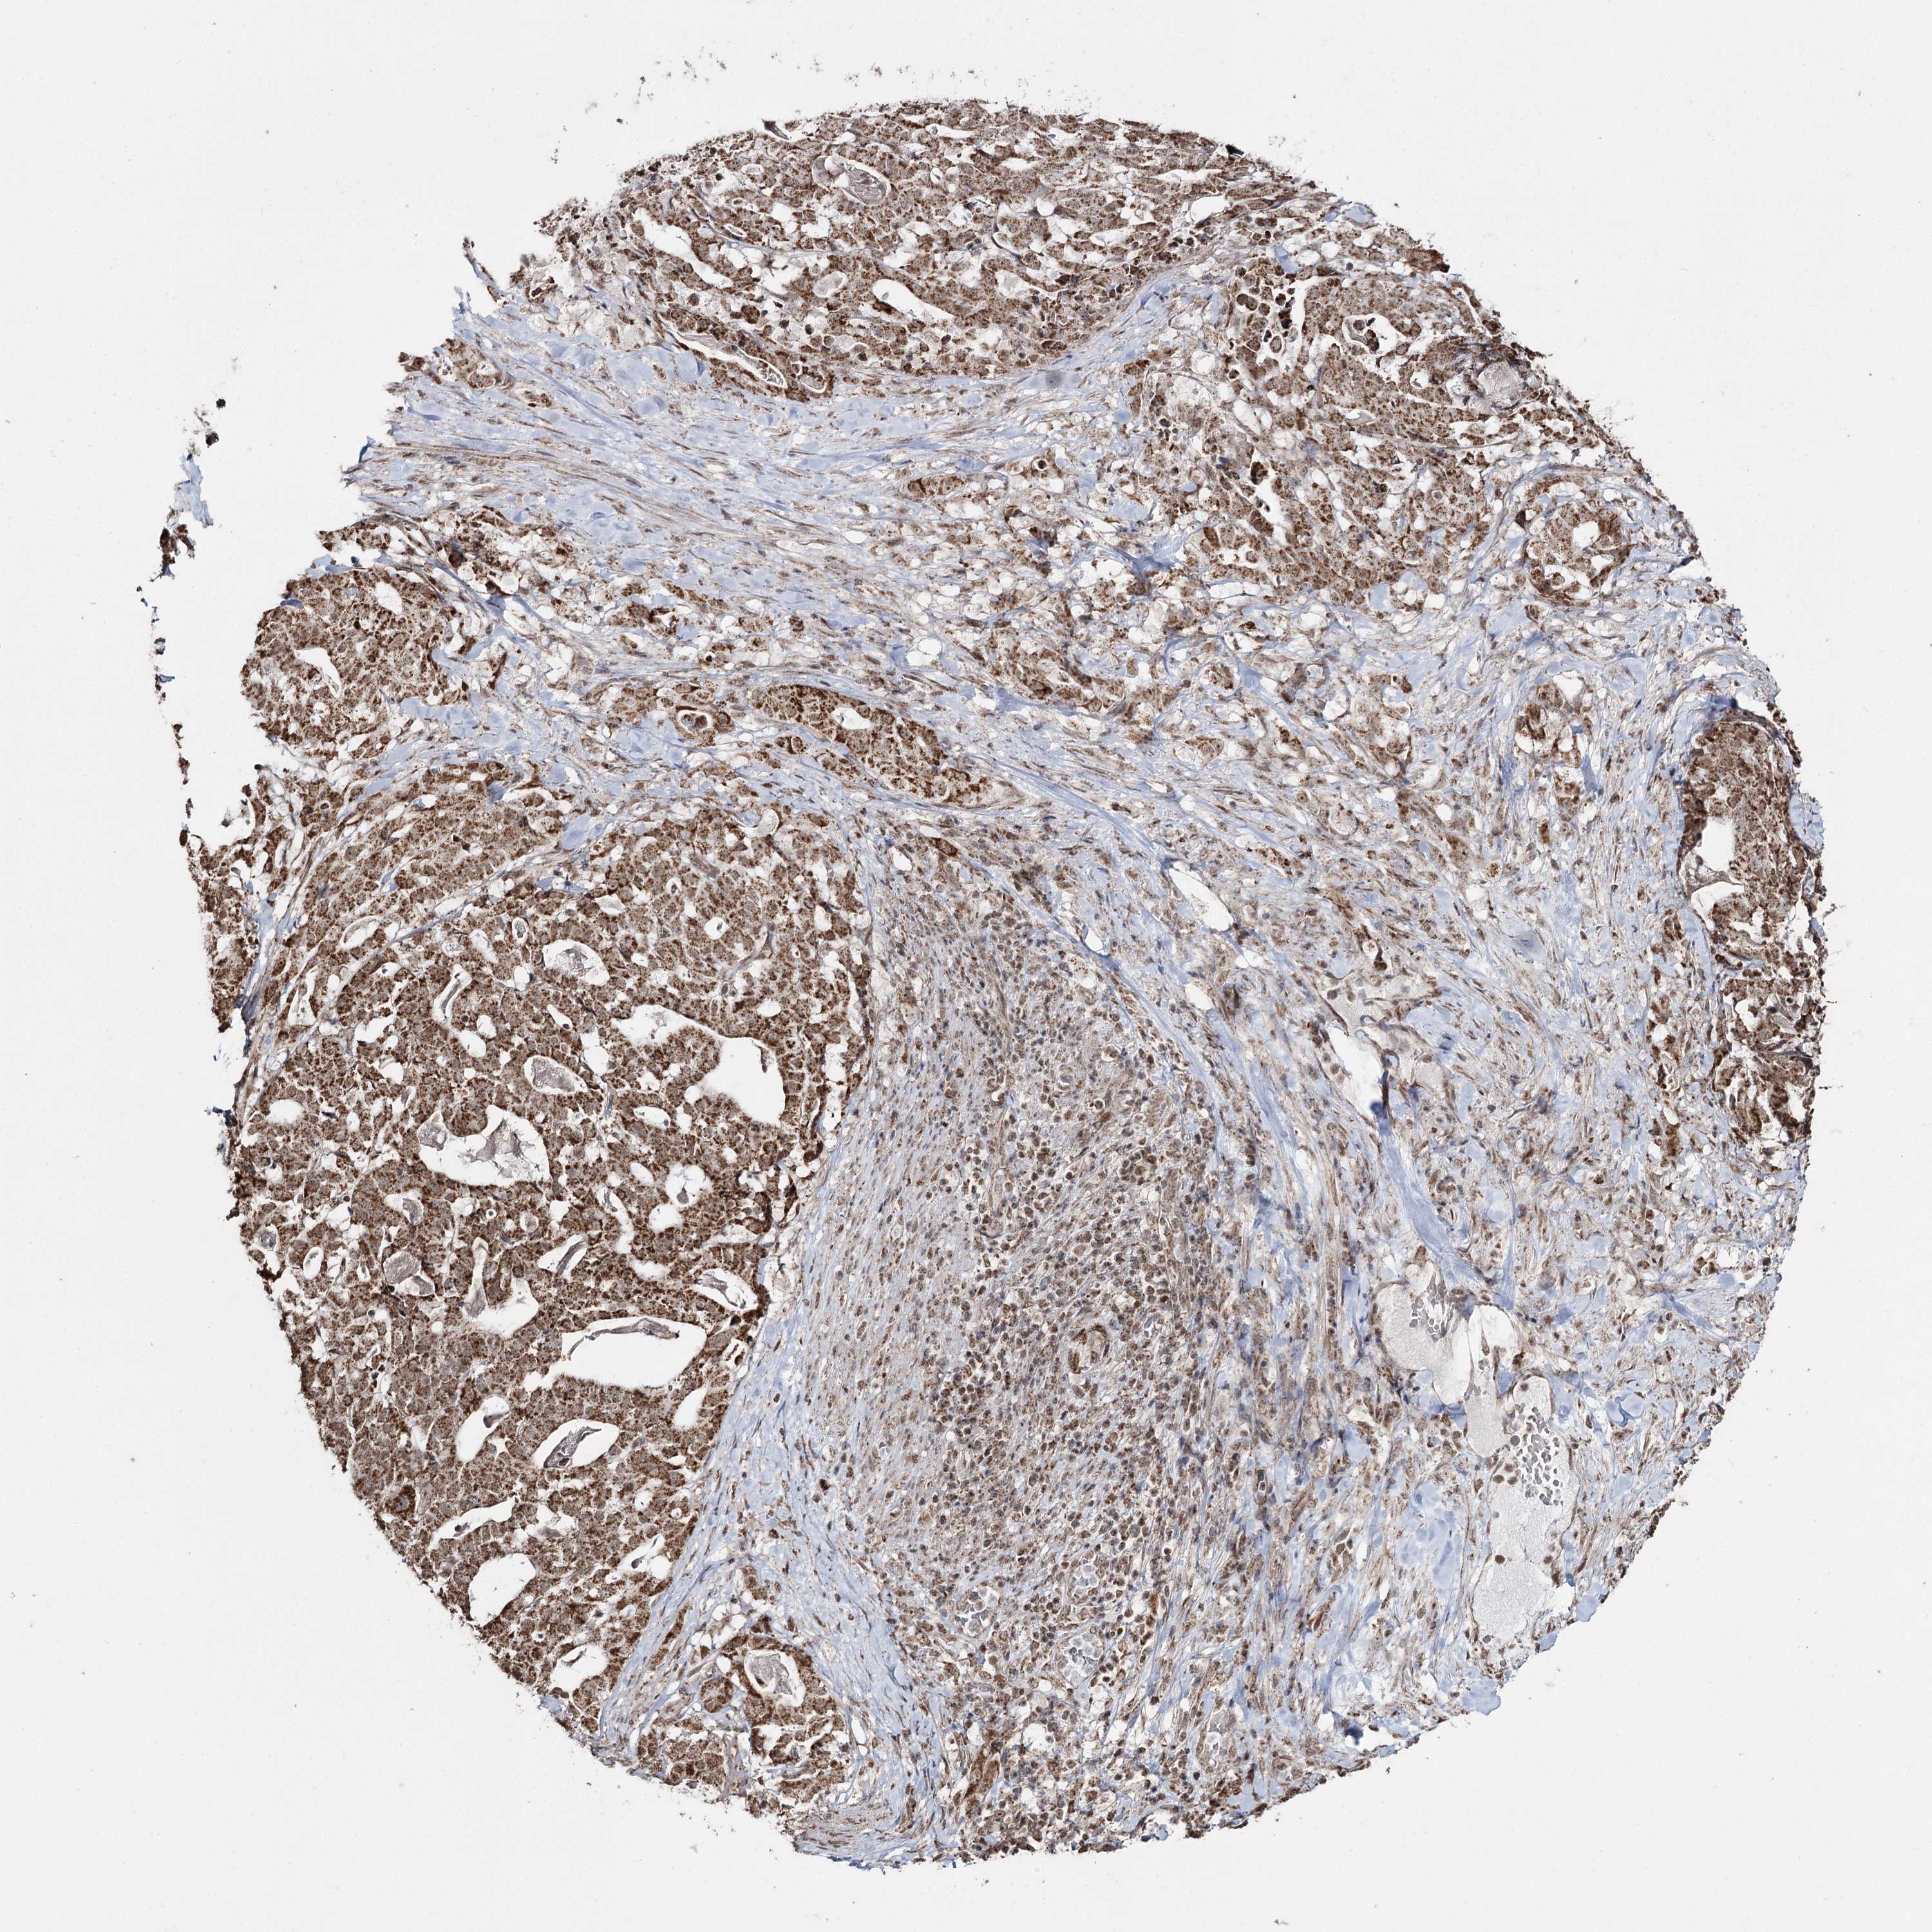

STOMACH CANCER - Protein expressioni

A mouse-over function shows sample information and annotation data. Click on an image to view it in a full screen mode. Samples can be filtered based on level of antibody staining by selecting one or several of the following categories: high, medium, low and not detected. The assay and annotation is described here.

Note that samples used for immunohistochemistry by the Human Protein Atlas do not correspond to samples in the TCGA dataset.

Antibody stainingi

Antibody staining in the annotated cell types in the current human tissue is reported as not detected, low, medium, or high, based on conventional immunohistochemistry profiling in selected tissues. This score is based on the combination of the staining intensity and fraction of stained cells.

Each image is clickable and will lead to virtual microscopy that enables deeper exploration of all samples and also displays staining intensity scores, fraction scores and subcellular localization as well as patient and tissue information for each sample.

Antibody HPA038484

Antibody HPA038485

Staining

High

Medium

Low

Not detected

Intensity

Strong

Moderate

Weak

Negative

Quantity

>75%

75%-25%

<25%

None

Location

Nuclear

Cytoplasmic/membranous

Cytoplasmic/membranous,nuclear

Adenocarcinoma, NOS

Adenocarcinoma, High grade